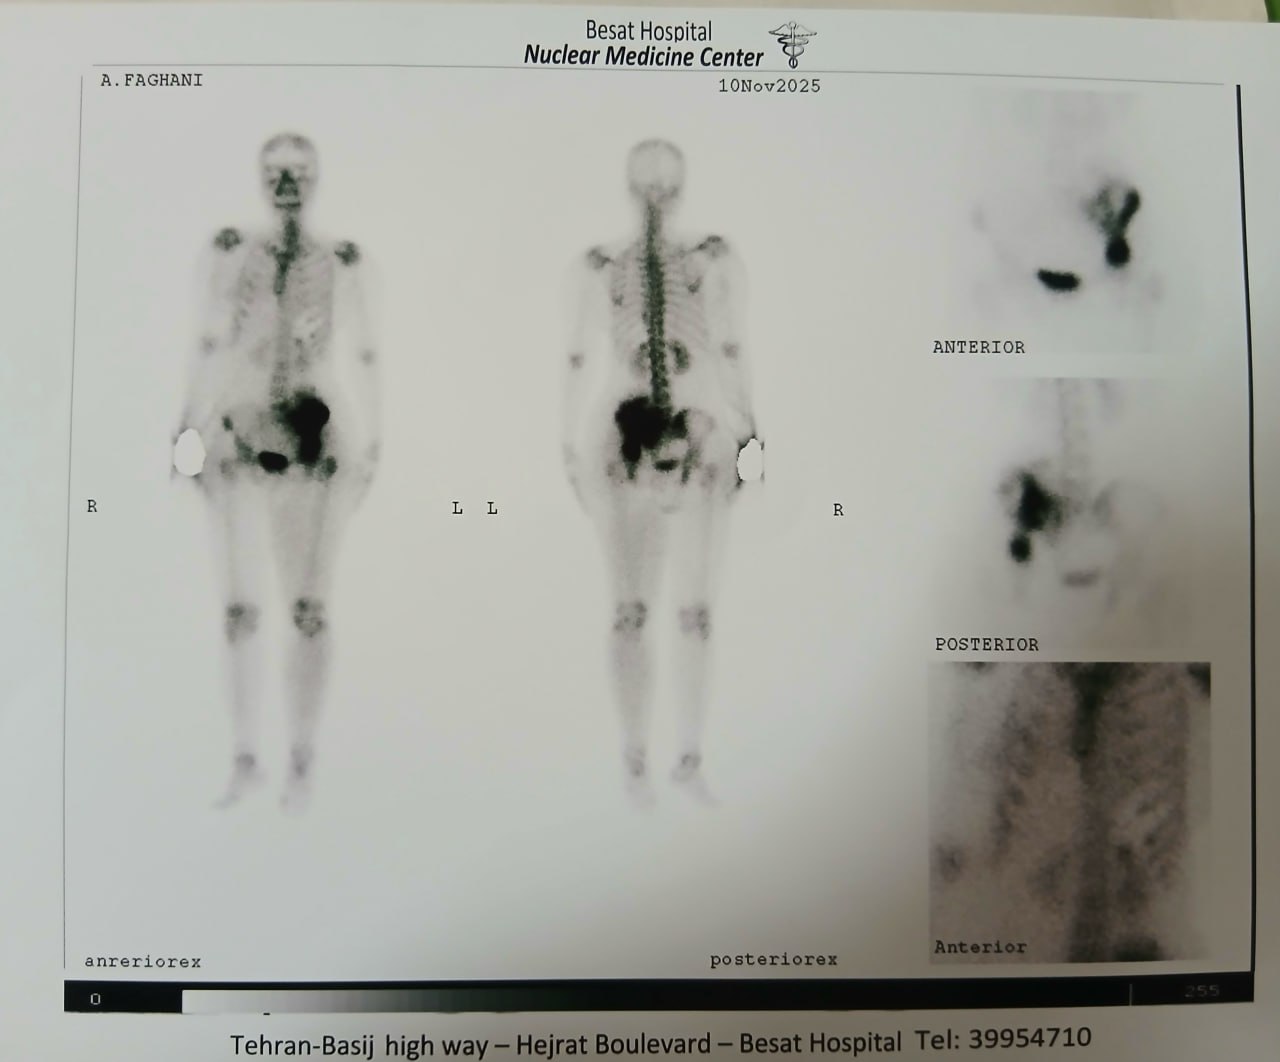

(تصویر مربوط به این مراجعه نیست) Other:

(تصویر مربوط به این مراجعه نیست) Other:

(تصویر مربوط به این مراجعه نیست) Other:

(تصویر مربوط به این مراجعه نیست) Other: